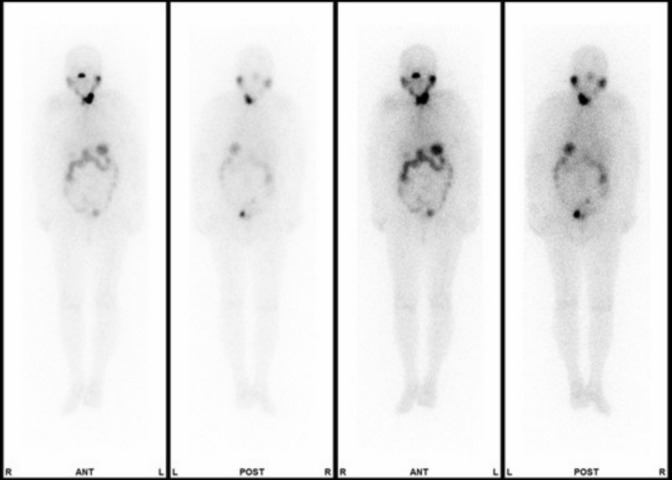

The half-life of radioactive iodine (RAI) is prolonged in patients with chronic kidney disease (CKD) because RAI is mainly excreted by the kidneys. There is little information on the RAI half-life in patients with dialysis-dependent CKD (CKDG5d). Estimating the RAI half-life in a patient's body provides important information for treatment planning. In this paper, we report a 68-year-old woman of CKDG5d who underwent postsurgical RAI therapy for papillary adenocarcinoma of the thyroid. We administered 15 mCi (0.56 GBq) RAI (131I) and continuously measured the dose equivalent rate. The results were summarized into hourly values of dose equivalent rate. Based on the measurements, we estimated the RAI half-life in the patient's body using a semi-log plot and linear regression analysis. In addition, we calculated the integrated doses for caregivers and the public using coefficients of 0.5 and 0.25, respectively. The half-life in the patient's body was 7.2 days (95% confidence interval, 4.8-14.4). The integrated doses for caregivers and the public were 0.23 mSv and 0.11 mSv, respectively. RAI therapy for a CKDG5d patient should be planned on the basis of the biological dynamics of 131I. Accumulation of more cases should lead to the establishment of a treatment strategy for patients undergoing RAI therapy and hemodialysis.